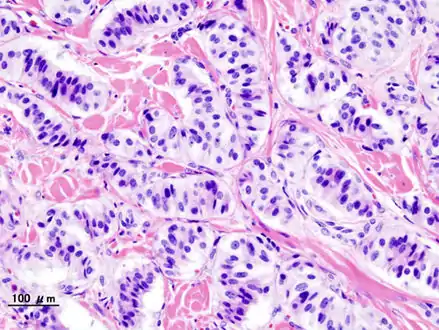

Pathology of pancreatic endocrine tumour (insulinoma).